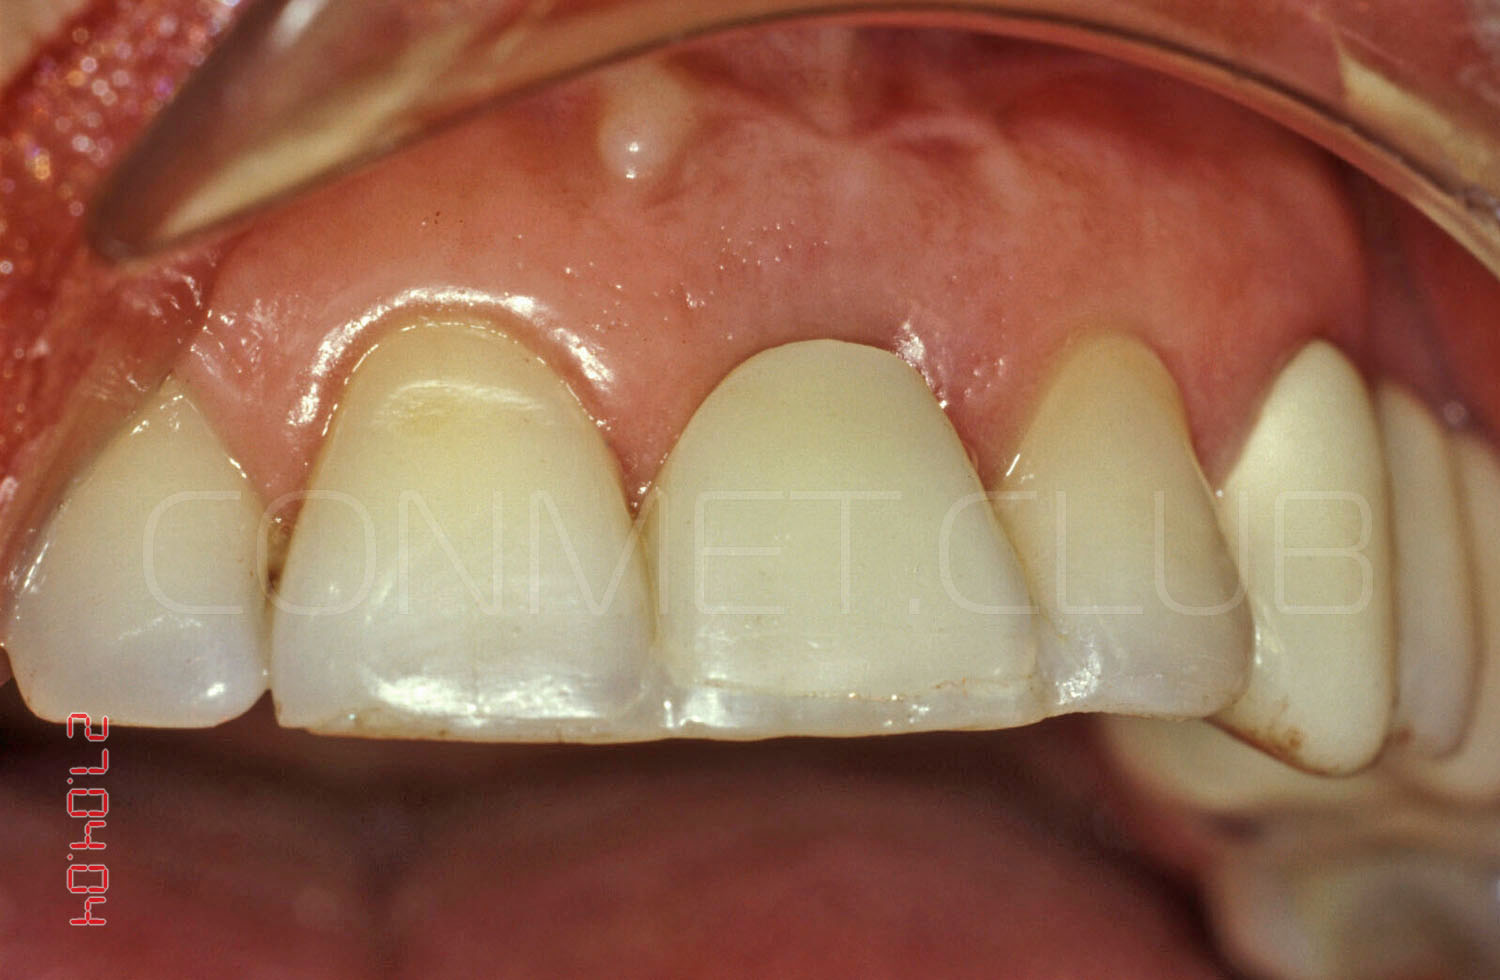

Ситуация в полости рта через 10 лет после операции. Обратите внимание на сохранность межзубных сосочков около имплантата и полное отсутствие рецессии десны на поддесневой, полированной части имплантата.